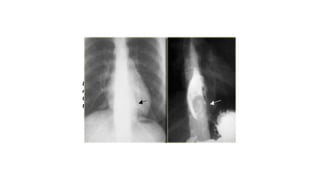

• Esophageal webs refer to an esophageal constriction caused by a thin mucosal membrane projecting into

the lumen.

oesophageal web

• More commonly occur in the cervical esophagus near

cricopharyngeus muscle than in the thoracic esophagus. They

typically arise from the anterior wall and never from the posterior

wall; they can also be circumferential 4. Occasionally, multiple webs

are visualized during maximal distension.

Multiple smooth tapered concentric narrowing of the cervical esophagus in keeping with esophageal webs.